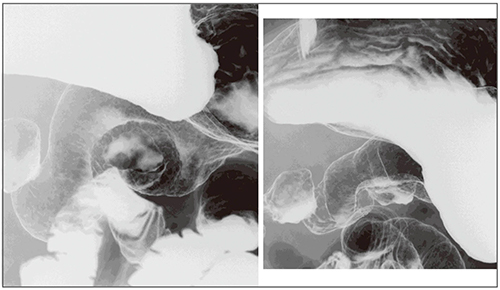

octaveによる胃癌の症例画像を提示する。図10は、体中部後壁に不規則な輪郭を示すはじき像が認められる例である。近接して表面模様を見てみると、隆起部と周囲粘膜の模様はよく似ている。最終病理診断は、0-IIa+IIc型、粘膜下層に浸潤する25×10mmの分化型癌であった。図11は、腹臥位二重造影第1斜位像で、噴門部に近い体上部前壁に粘膜集中が観察された例である。周囲正常粘膜と比べて病変部粘膜には濃淡の差が認められ、その輪郭には微細な線状陰影が描出されていた。0-Ⅱc型、粘膜下組織の浅層に浸潤する45×21mmの分化型癌であった。図12は、胃角部前壁小彎のはっきりとした凹凸が目立つ病変である。漿膜外に浸潤する未分化型の3型進行癌であった。

図12 3型、56×50mm、por2=sig>tub2、SE